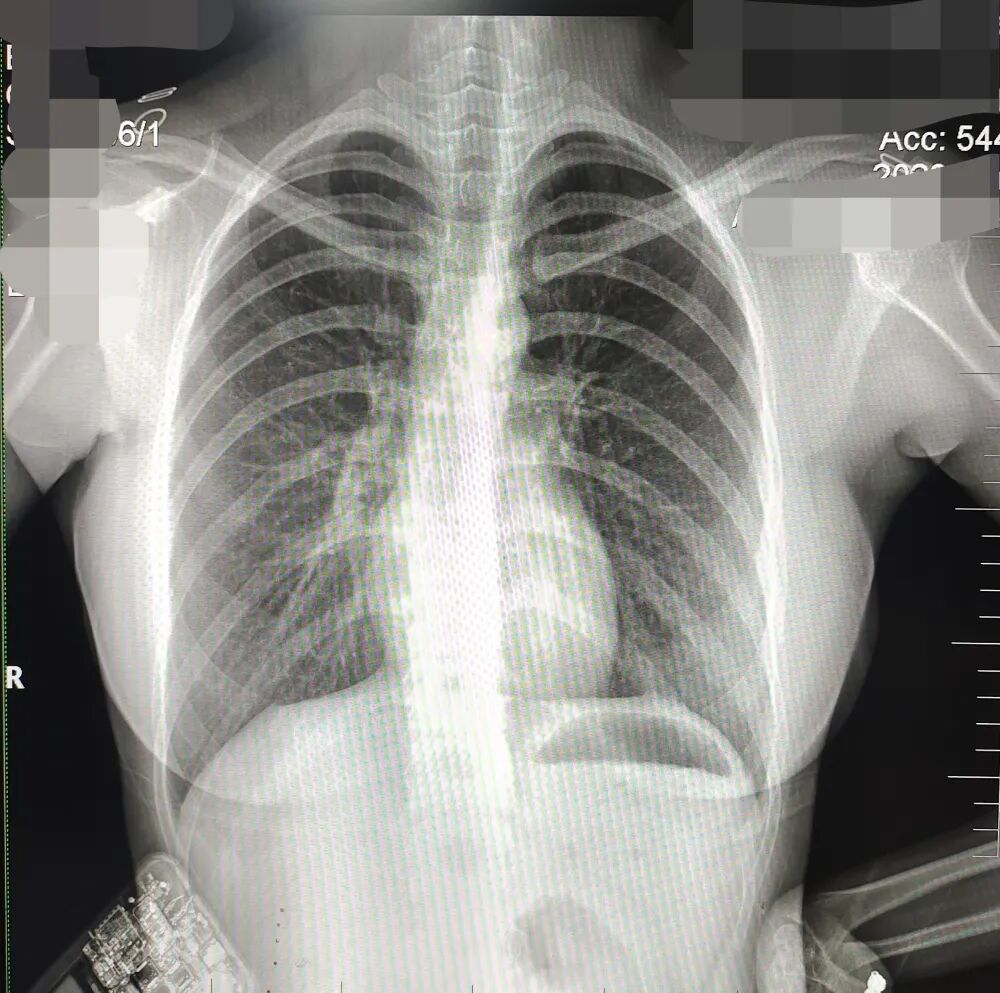

DR胶片为什么分尺寸借DR成像原理详解胸部正位摄片技术参数_https://www.jmylbn.com_新闻资讯_第8张

缺陷:两肩胛骨未拉开肺野之外,吸气不完全,且存在金属饰品遮挡。

解决:去除金属饰品及内衣后重新按标准体位摄片即可。